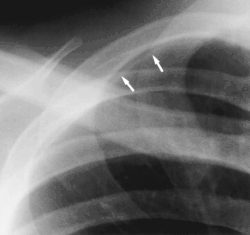

- Clavicular companion shadow is a thin soft-tissue stripe along the upper edge of the clavicle.[1]